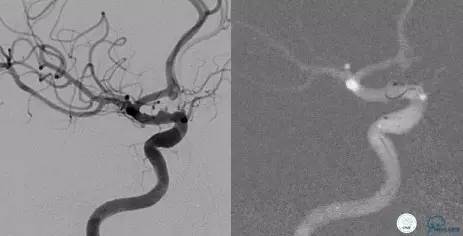

Case1 右ICA多发床突旁动脉瘤